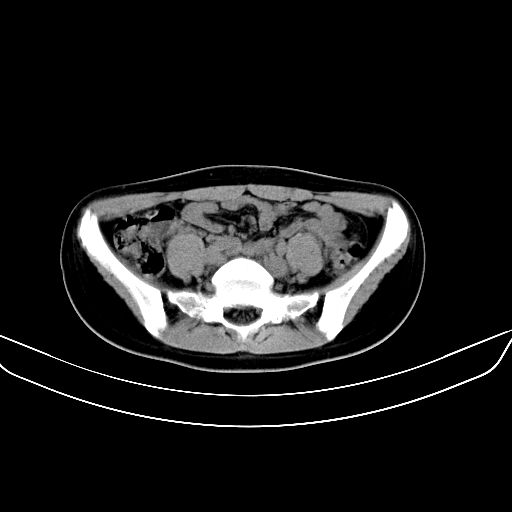

以下是引用zsl6918在2008-7-11 21:40:00的发言:[br]双侧骶髂关节骨质破坏以下三分之一为主,符合强直性脊柱炎表现

以下是引用zhangzhongshou在2008-7-11 21:41:00的发言:[br]患者是女性,hla-b27抗原(—),首先不太考虑强直性脊柱炎,建议查类风湿因子,骶髂关节改变考虑类风湿性关节炎可能性大,建议进一步检查。